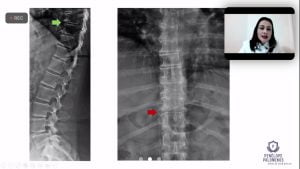

Discussão de casos clínicos: Artrite Psoriásica e iJAK

No dia no 31 de agosto a Sociedade de Reumatologia de Brasília realizou a 3ª Reunião Científica – discussão de casos clínicos. No encontro virtual moderadora Penélope Palominos falou sobre o tema: Artrite Psoriásica e iJAK.